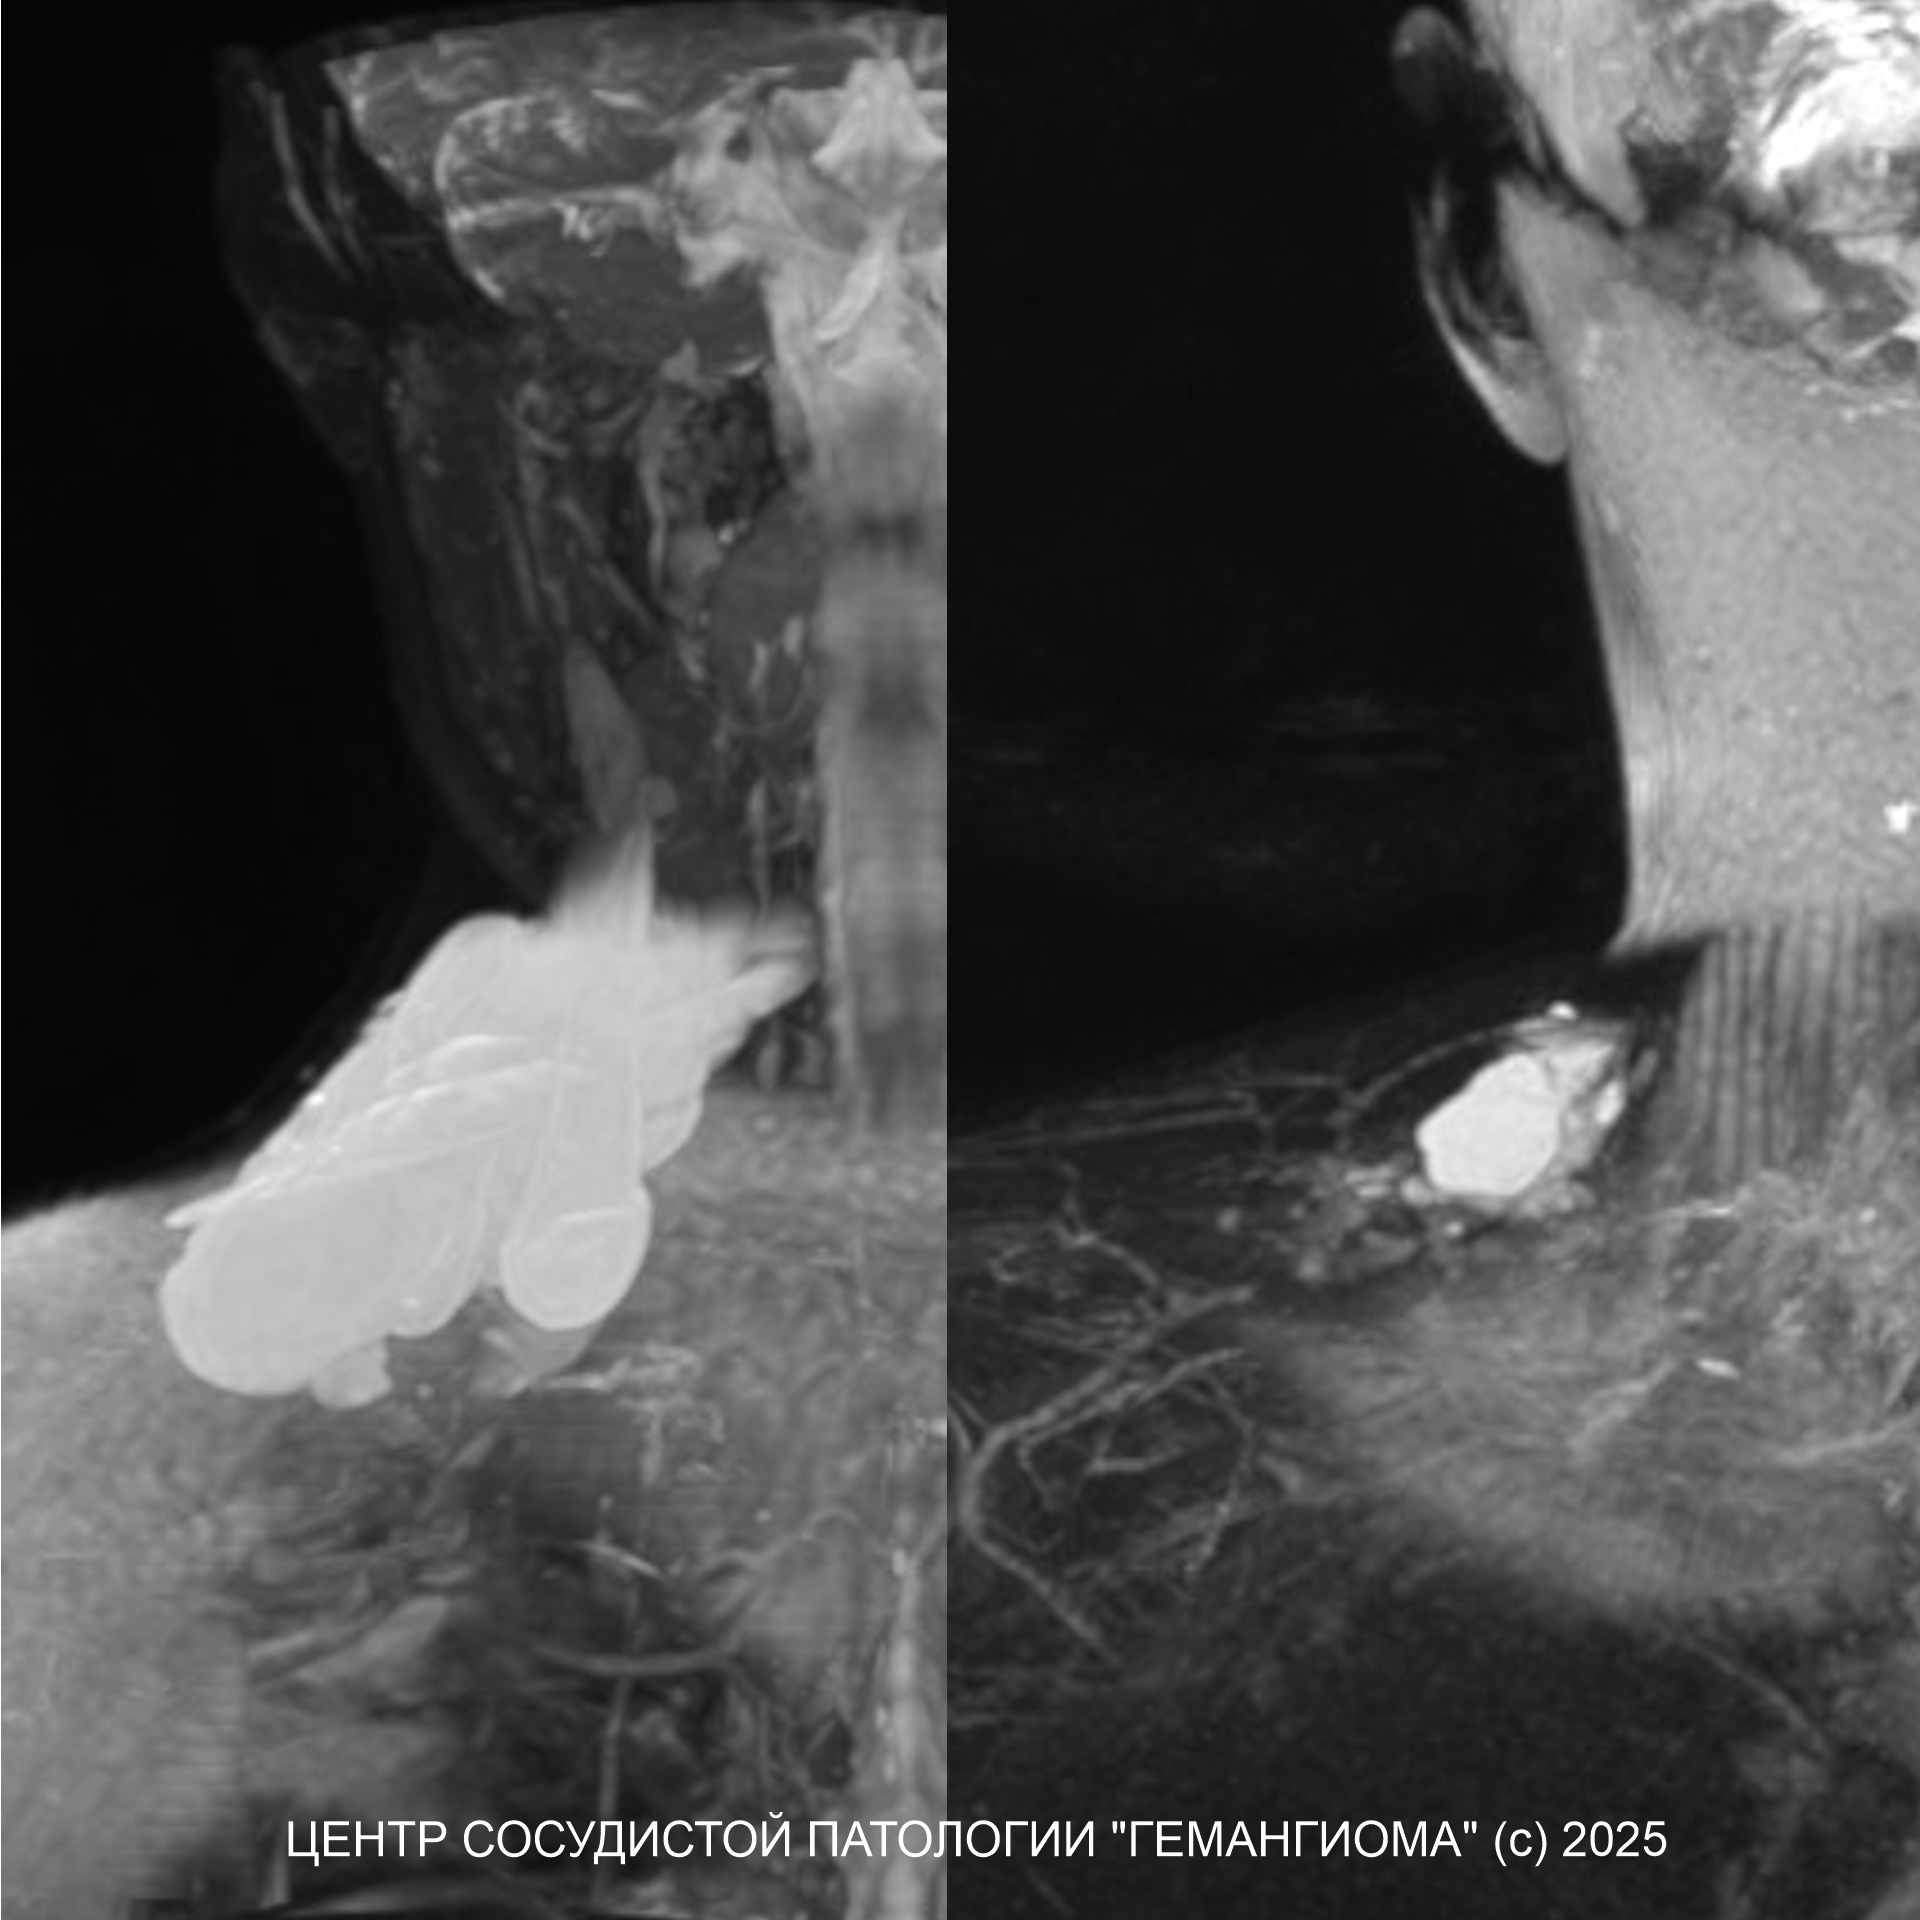

На изображении 3D МРТ пациента с лимфатической мальформаций в области основания шеи справа, до и после одного сеанса лечения препаратом Гемоблок.